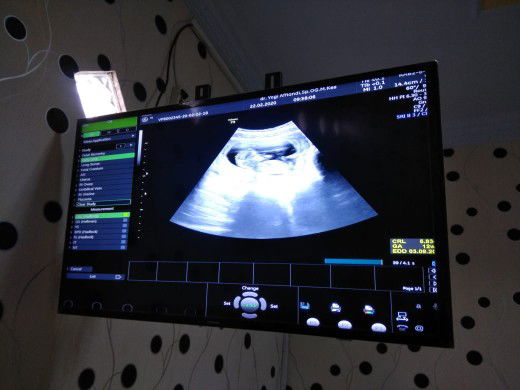

USG pertamaku

Assalamualaikum bunda... Ini usg pertamaku di usia kandungan 12 minggu 2 hari, alhamdulillah kta dokternya bayinya sehat aktif banget. Ada ngga bunda yg HPL 04 September ? Udah ngerasain apa aja bun ? sharing yuk...